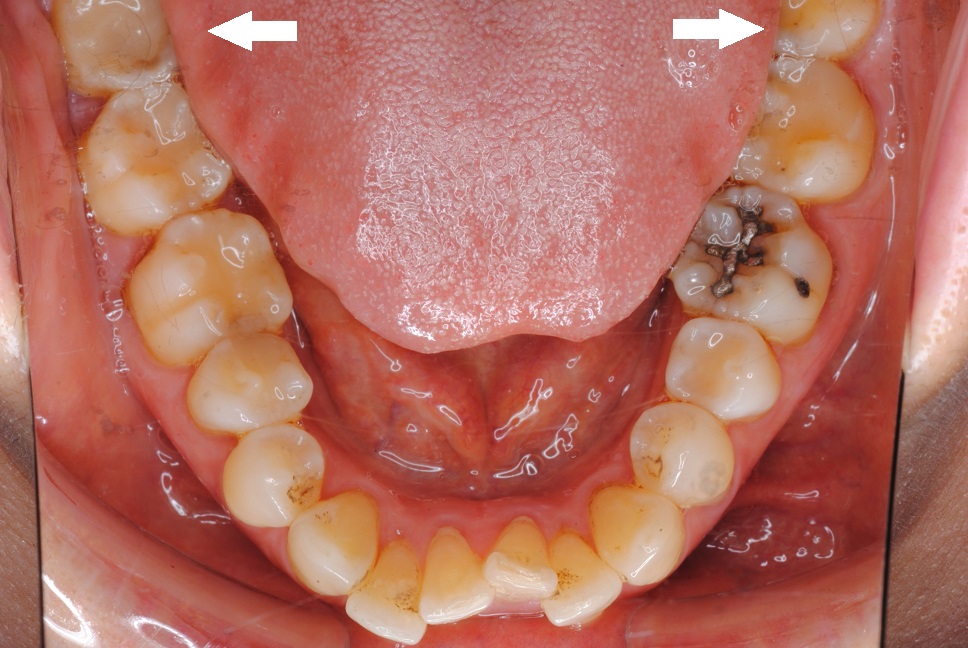

治療前

この症例では矯正装置の装着前に上下顎すべての親知らずの抜歯を先行しました。特に下顎の親知らずを抜歯した直後に、患者さまが ”歯が押されている感じがなくなって楽です” ということを話されていました。

治療後